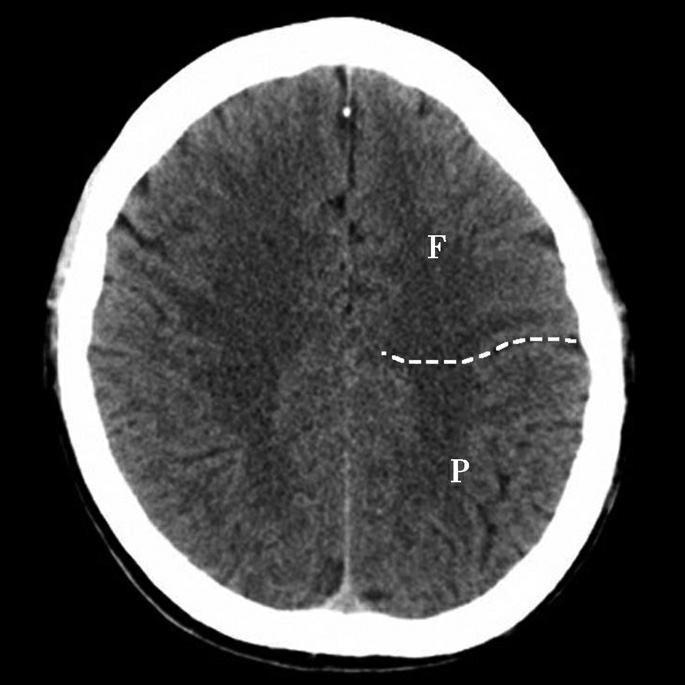

重要结构:放射冠、胼胝体体部、侧脑室顶部、中央沟、扣带回(图1-2-40、图1-2-41)。

图1-2-40 放射冠层面

A.横断面;B.横断面标注

1.上矢状窦;2.大脑镰;3.额叶;4.颞肌;5.扣带回;6.中央前沟;7.中央前回;8.中央沟;9.中央后回;10.中央后沟;11.放射冠;12.胼胝体体部;13.侧脑室顶部;14.顶叶;15.顶枕沟;16.枕叶

图1-2-41 脑叶划分示意图

F.额叶;O.枕叶;P.顶叶;C.扣带回

双侧脑室体顶部间以胼胝体体部及扣带回相隔。当胼胝体发育不良或缺如时,双侧侧脑室间距可缩小,可合并脂肪瘤(图1-2-42)。侧脑室体顶部周围白质呈扇形放射状分布连接大脑皮质及皮质下诸结构,故称放射冠。大脑纵裂内有大脑镰及其前、后端的上矢状窦断面构成中线结构。大脑半球内侧面由前至后有额内侧回、扣带沟、扣带回、顶下沟、楔前叶、顶枕沟和楔叶;大脑半球外侧面由前至后依次为额上回、额中回、额下回、中央前回、中央沟、中央后回、缘上回、角回和枕叶。

中央沟位于半球中部稍偏前,位置大约平侧脑室顶部前1/3处,可作为额顶叶分界并识别中央前、后回的标志。在半球内侧面后部可见一较深的脑沟为顶枕沟,此沟的后方为枕叶。